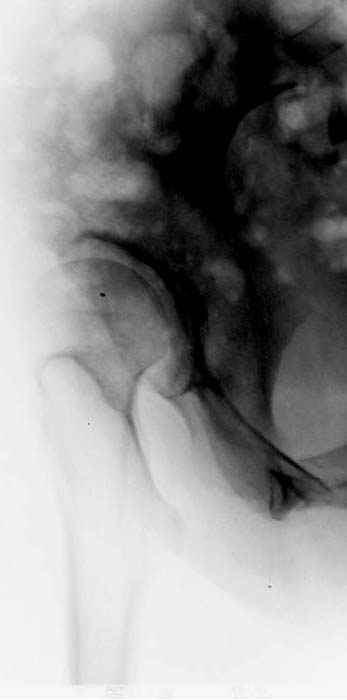

Рис.1 Трехмерная модель тазобедренного сустава с аналогом связки головки бедра. Заметно, что из торца головки выходит капроновый шнур, который с одной стороны прикрепляется к ножке бедренной части модели, а другой его конец, проходя через головку и прикрепляется к вертлужной части модели. Динамометр оказывается не нагруженным, так как аналог связки головки бедра замыкает подвижный узел модели во фронтальной плоскости.